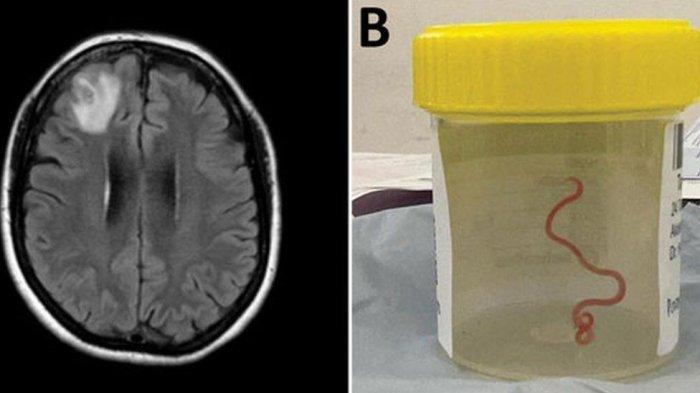

Ada seekor cacing sepanjang 8 cm yang hidup di bagian otak perempuan yang tak disebutkan namanya tersebut.

Dokter yang saat itu melakukan CT-Scan menemukan ada hal yang aneh di otak bagian kanan perempuan tersebut.

Ia pun kemudian dirujuk ke RS Canberra untuk menjalani MRI.

Dari situlah kemudian diputuskan untuk melakukan operasi bedah otak.

Saat itulah para dokter bedah dibuat tercengang lantaran mereka menemukan seekor cacing parasit yang hidup di otak pasien tersebut.